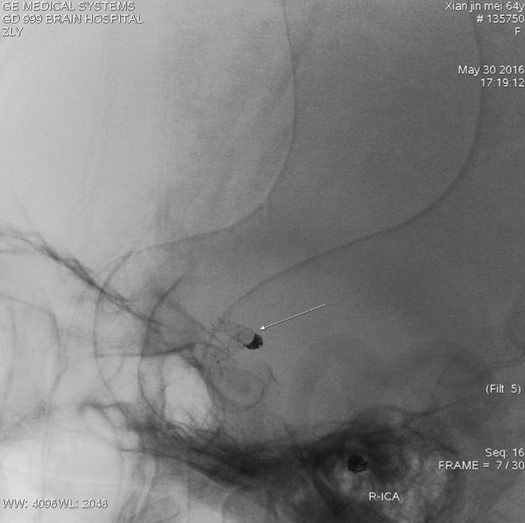

右侧颈内动脉造影:右侧后交通动脉瘤,大小约2.0×2.5mm;

Livs(212517)支架辅助栓塞后交通动脉瘤,动脉瘤不显影

栓塞后不减影,弹簧圈形态符合动脉瘤形态

支架完全打开,与血管贴壁良好,覆盖瘤颈口满意